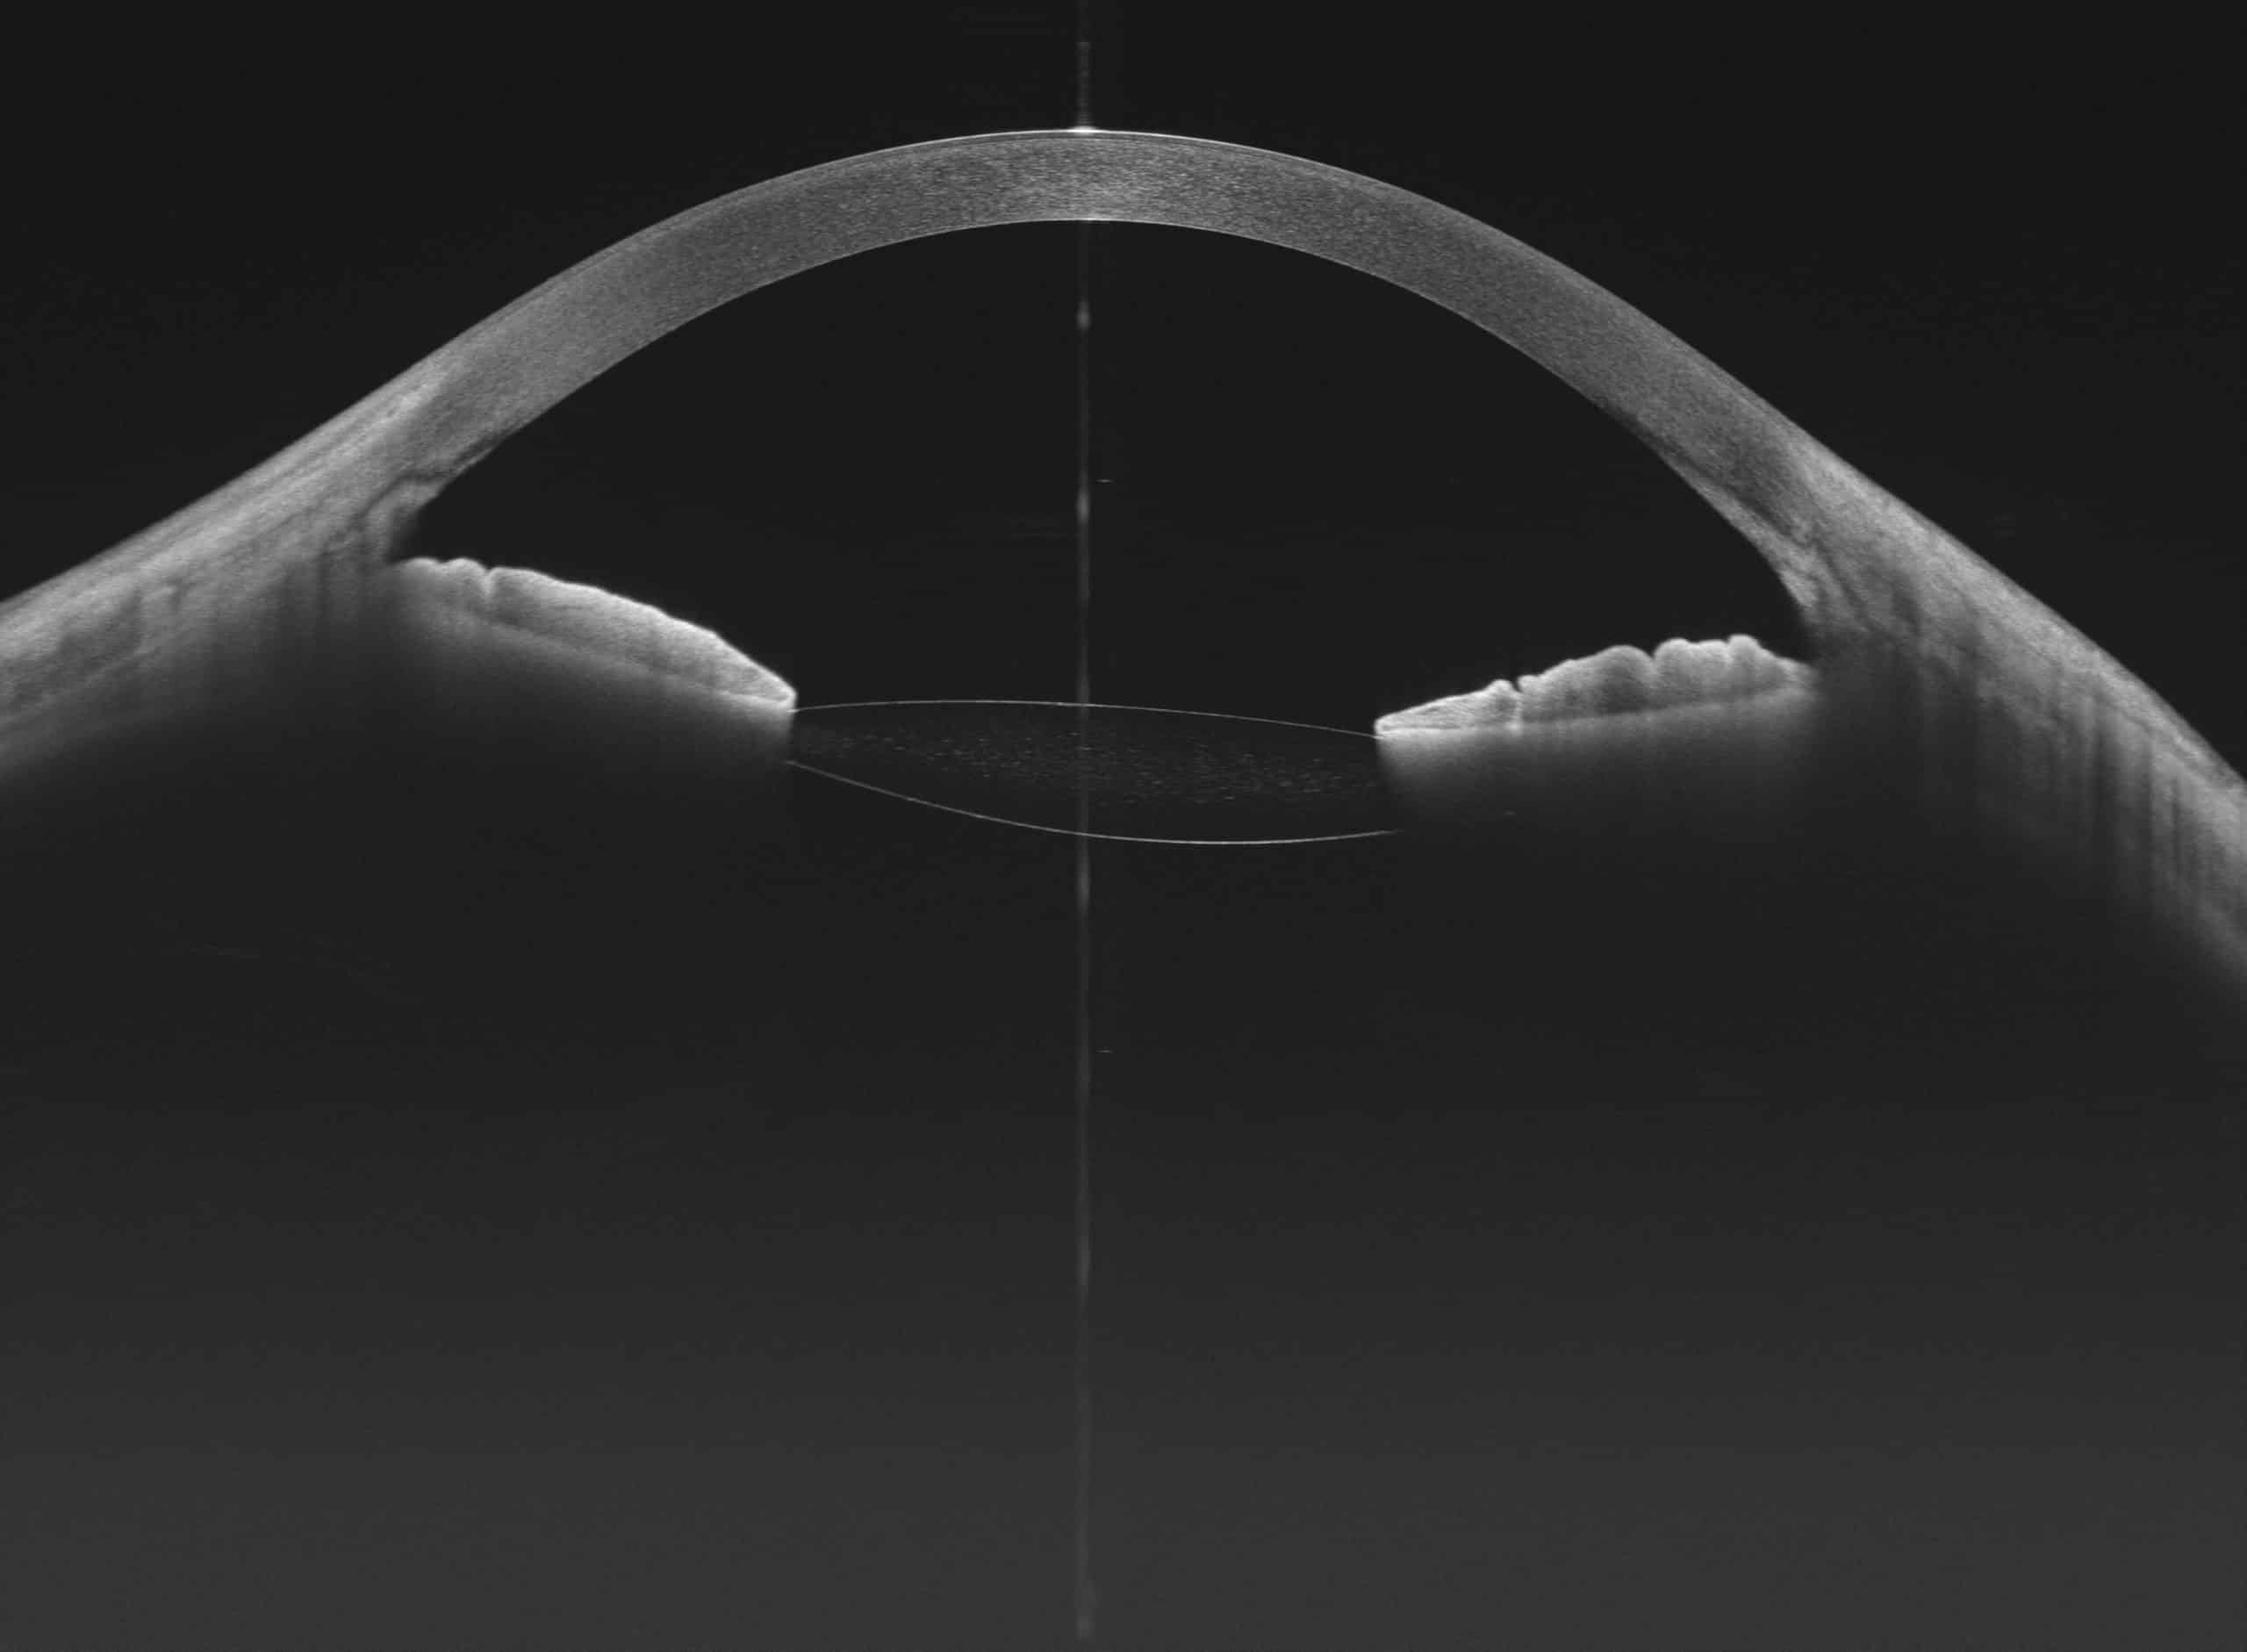

100kHz speed full-range swept-source OCT for anterior and posterior

- HD Anterior Scan with Anterior OCTA

- 15mm Scan depth anterior